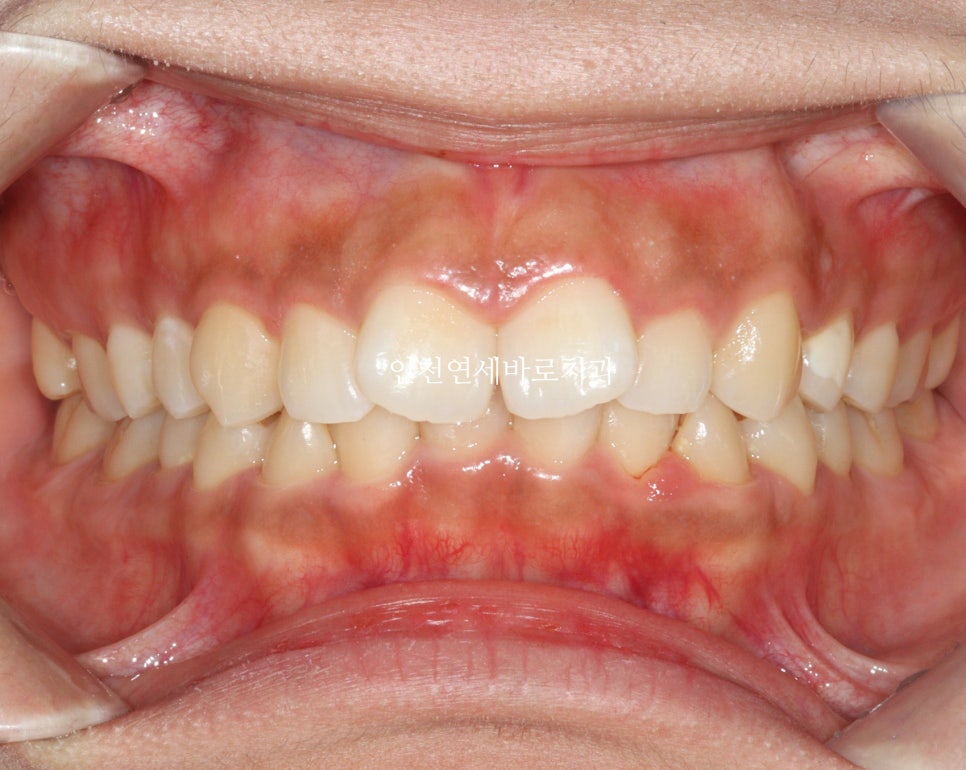

전후 비교입니다

전 후 교합의 비교입니다.

안정적으로 교합이 형성되었습니다

교정 끝난 직후의 사진이라 아주 약간은 제 마음에 안드는 부분이 있지만

11월말에 내원하시어 #비베라 제작을 할때 체크해보면 모두 해결이 되어있을 겁니다.